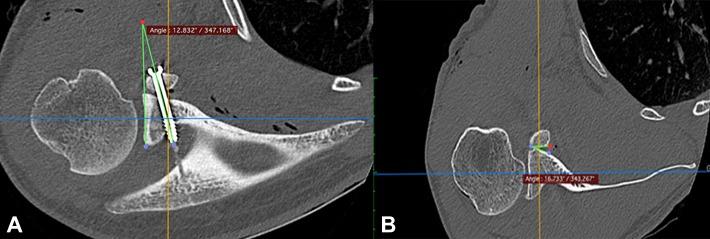

A total of 49 patients who underwent a Latarjet procedure for the treatment of recurrent anterior shoulder instability were prospectively included; the procedure was performed with the freehand technique in 22 patients (group 1) and with use of a parallel drill guide during screw placement in 27 patients (group 2). All patients underwent a postoperative computed tomography scan with the same established protocol. The scans were used to evaluate and compare the position of the CG in the sagittal and axial planes, the direction of the screws (α angle), and overall contact of the graft with the anterior surface of the glenoid after the 2 surgical techniques.

The CG was placed >60% below the native glenoid equator in 23 patients (85.2%) in group 2, compared with 14 patients (63.6%) in group 1 ( = .004). In the axial plane, the position of the CG in group 2 patients was more accurate (85.2% and 88.9% flush) at the inferior and middle quartiles of the glenoid surface ( = .012 and .009), respectively. Moreover, with the freehand technique (group 1), the graft was in a more lateral position in the inferior and middle quartiles ( = .012 and .009, respectively). No differences were found between groups 1 and 2 regarding the mean α angle of the superior (9° ± 4.14° vs 11° ± 6.3°, = .232) and inferior (9.5° ± 6° vs 10° ± 7.5°, = .629) screws. However, the mean contact angle (angle between the posterior coracoid and the anterior glenoid surface) with the freehand technique (3.8° ± 6.8°) was better than that of the guide (8.55° ± 8°) ( = .05).

Compared with the classic freehand operative technique, the parallel drill guide can ensure more accurate placement of the CG in the axial and sagittal planes, although with inferior bone contact.

前瞻性纳入49例行Latarjet手术治疗复发性前肩关节不稳的患者;22例患者采用徒手技术进行手术(第1组),27例患者在螺钉置入时使用平行钻导向器(第2组)。所有患者均按照相同的既定方案进行术后计算机断层扫描。扫描用于评估和比较两种手术技术后CG在矢状面和轴平面上的位置、螺钉方向(α角)以及移植骨与肩胛盂前表面的整体接触情况。

第2组23例患者(85.2%)的CG放置在天然肩胛盂赤道下方>60%,而第1组为14例患者(63.6%)(P = 0.004)。在轴平面上,第2组患者的CG在肩胛盂表面下四分位和中四分位的位置更准确(分别为85.2%和88.9%平齐)(P = 0.012和0.009)。此外,采用徒手技术(第1组)时,移植骨在下四分位和中四分位处于更外侧的位置(分别为P = 0.012和0.009)。第1组和第2组在上部螺钉(9°±4.14°对11°±6.3°,P = 0.232)和下部螺钉(9.5°±6°对10°±7.5°,P = 0.629)的平均α角方面未发现差异。然而,徒手技术的平均接触角(喙突后部与肩胛盂前表面之间的角度)(3.8°±6.8°)优于导向器的平均接触角(8.55°±8°)(P = 0.05)。

与传统的徒手手术技术相比,平行钻导向器可确保CG在轴平面和矢状面上更精确的放置,尽管骨接触较差。